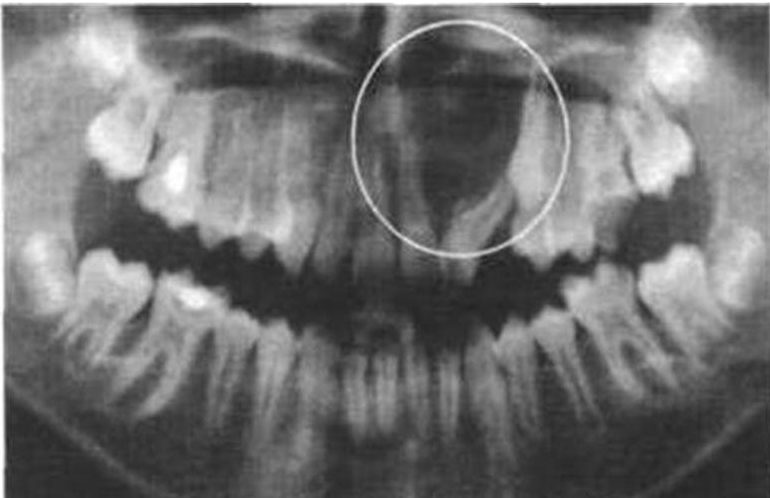

Чаще всего происходит следующее. Когда пациент обращается к стоматологу с определёнными жалобами, специалист проводит первичный осмотр ротовой полости и, если это необходимо, назначает рентгенографическое исследование.

Если в костной ткани обнаруживаются посторонние элементы, пациента направляют на консультацию к онкологу, который должен вынести окончательное заключение.

В некоторых случаях выявляется рак корня зуба, который часто путают с прикорневой кистой.

Киста представляет собой полость, заполненную мёртвыми клетками эпителия и погибшими бактериями. Наиболее распространённой причиной появления корневой кисты является попадание инфекции в корневые каналы. Воспалительный процесс остаётся локализованным, так как ограничивается стенками полости. Однако постоянное увеличение её объёма может привести к постепенному разрушению костной ткани.

В дальнейшем киста может трансформироваться в злокачественную опухоль. Такой сценарий заставляет врачей прибегать к удалению зуба вместе с опухолью.